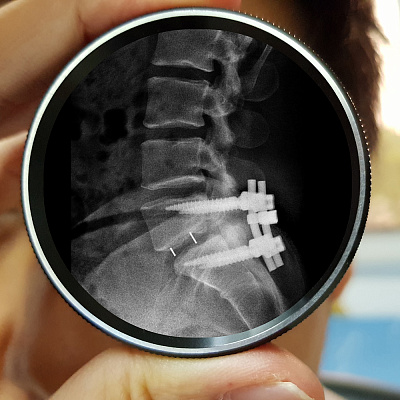

Стабилизирующая операция для усиления опорной функции позвоночника — наложение металлических скоб после проведения расширения позвоночного канала;

Микрохирургическая декомпрессия и использование фиксирующих систем для укрепления позвоночного столба после ликвидации стеноза; функция сгибания и разгибания позвоночника сохраняется;